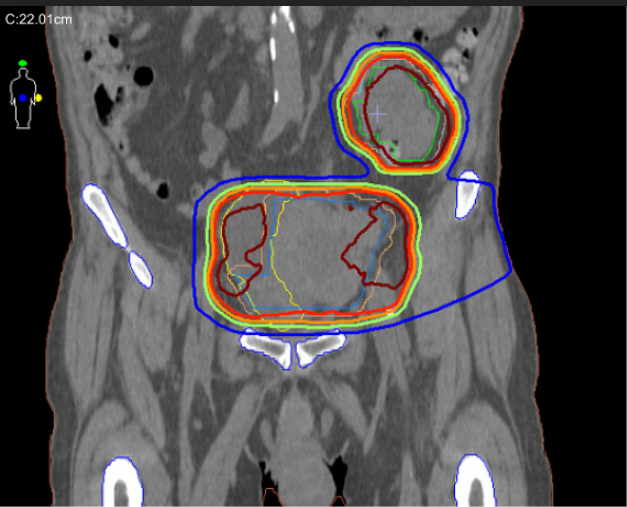

Metastatic carcinoma, dose constraints, liver disease, hypofractionation, ER+ breast cancer, hypothermia treatment, small bowel treatment, metastatic breast cancer

Palliative treatment, advanced rectal cancer, local regional disease, dose, systemic therapy, hemoptysis, fibrosis, large endometrial mass

stomach METs, melanoma, palliatve care, metastatic, bleeding stomach, immunotherapy, radiation therapy, lymphoma, low grade, locally recurrent, first principles, lung tumors, steroids, prednizone, dexamethasone, oral morphine, morphine drip, vaginal discharge, MRI, primary tumors, lymph nodes, me...